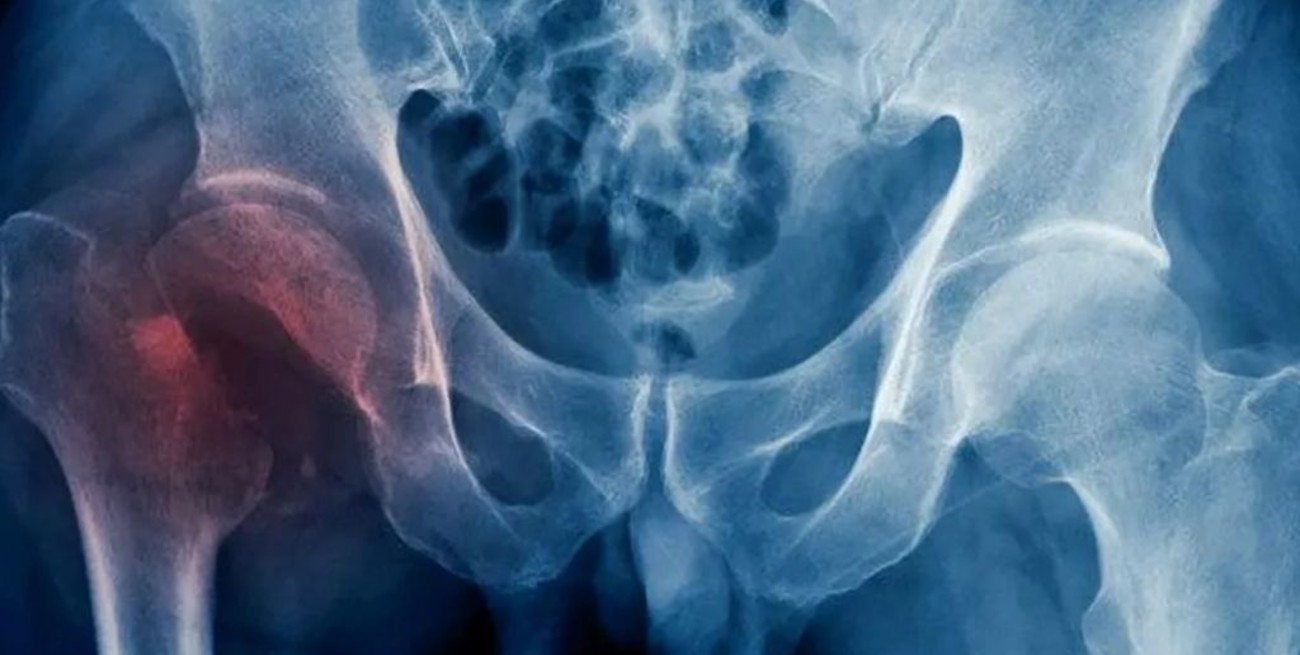

Según explicó, estas fracturas se suelen dar normalmente en cuatro zonas y generan las denominadas “fracturas por fragilidad”: la cadera, la columna, la muñeca (radio distal) y el hombro (húmero proximal) que, ante traumas mínimos en un paciente con osteoporosis, pueden generar fracturas.

La osteoporosis del anciano suele ocasionar fracturas de huesos largos, en su mayoría el fémur, siendo responsable de las típicas fracturas de cadera.